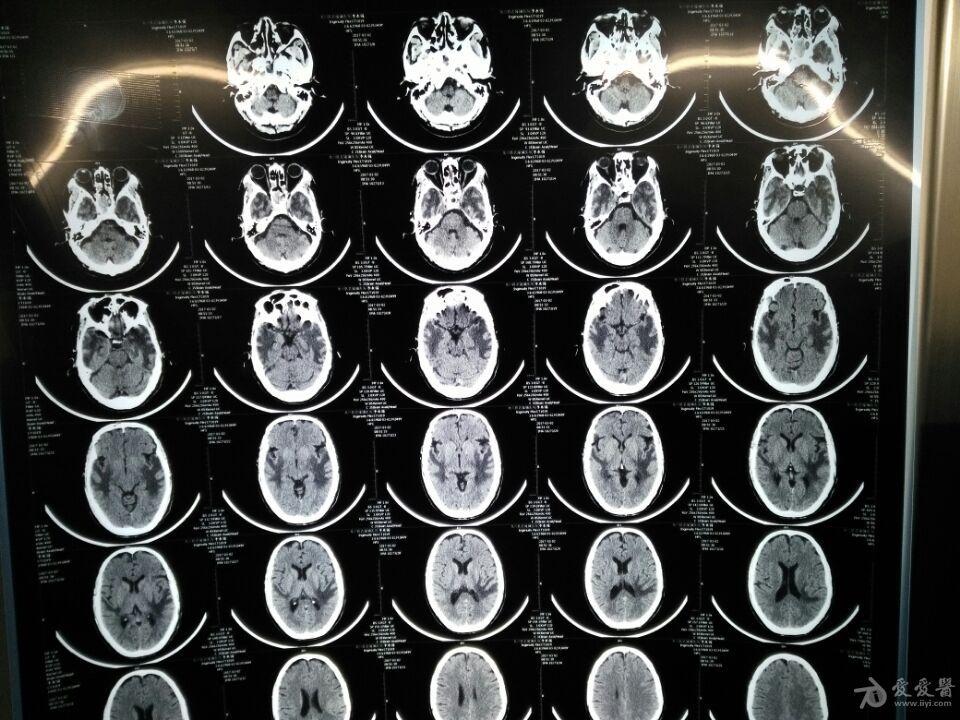

半年前无明显诱因出现吐字不清,右眼模糊,看看片子 - 神经内科讨论版

图片尺寸960x720